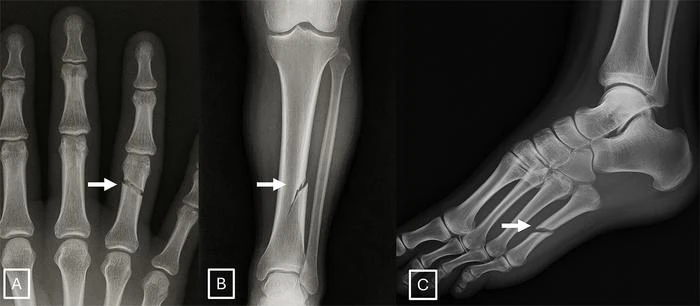

The study identified common features of synthetic X-rays.

"Deepfake medical images often look too perfect,” Dr. Tordjman said. “Bones are overly smooth, spines unnaturally straight, lungs overly symmetrical, blood vessel patterns excessively uniform, and fractures appear unusually clean and consistent, often limited to one side of the bone."